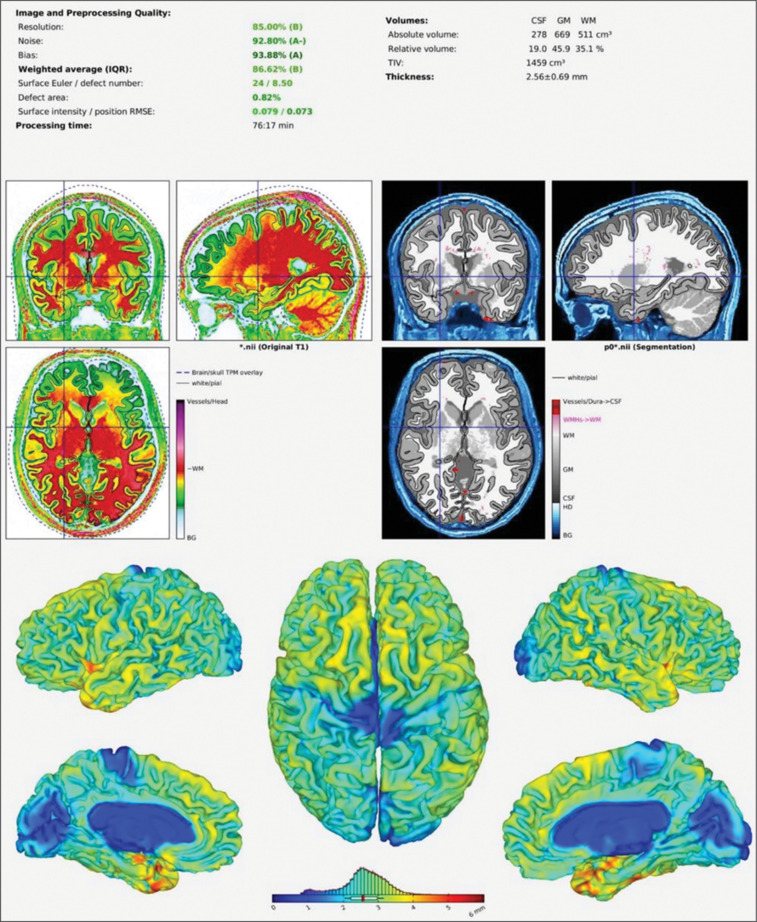

Materials and methods: In this cross-sectional study, 102 sedentary adults (34 normal weight, 34 overweight, 34 obese) underwent brain MRI scans. Grey matter, white matter, cerebrospinal fluid, and regional brain volumes were measured. Correlations between BMI, physical activity levels, and brain volumes were analyzed within each weight group.

Results: No significant differences in overall or regional brain volumes were found between groups. In the normal weight group, BMI positively correlated with right superior temporal gyrus (rSTG) volume (r = 0.358, P < 0.05) and grey matter volume (r = 0.367, P < 0.05). In the obese group, BMI negatively correlated with rSTG volume (r = -0.467, P < 0.01) and positively correlated with self-reported physical activity (r = 0.395, P < 0.05). No significant correlations were observed in the overweight group.